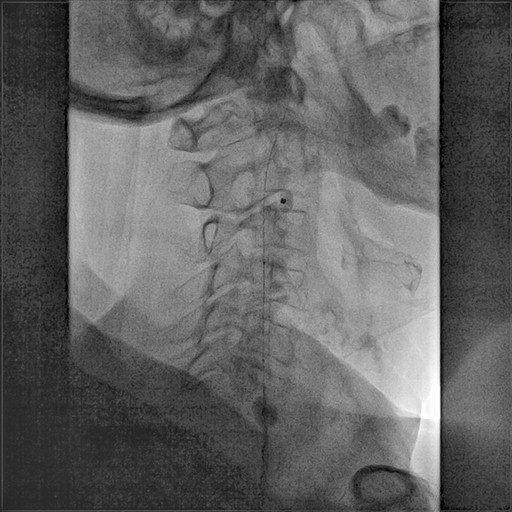

3. Posizionamento del Catetere:

• Utilizzando tecniche di imaging radiologico, il catetere viene posizionato nella carotide interessata, oltre la placca aterosclerotica.

4. Dilatazione e Stenting:

• Una volta raggiunta la zona ristretta, viene gonfiato un palloncino per dilatare l'arteria.

• Successivamente, viene posizionato uno stent, una piccola rete metallica, per mantenere l'arteria aperta e prevenire future occlusioni.